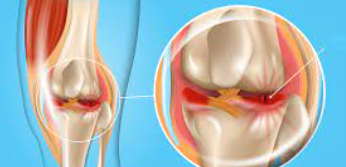

무릎 연골 손상의 가장 대표적인 증상은 무릎 관절 부위의 통증입니다. 초기에는 운동 후나 장시간 활동 후에만 나타나지만, 손상이 진행되면서 일상적인 움직임에서도 통증이 발생합니다. 특히 계단을 오르내리거나 쪼그려 앉는 동작에서 통증이 심화되는 특징을 보입니다.

연골 손상으로 인한 통증은 날카로운 찌르는 듯한 통증보다는 둔하고 깊은 곳에서 느껴지는 통증의 양상을 보입니다. 무릎을 직접 눌렀을 때 압통이 느껴지며, 특히 무릎뼈 주변과 관절선 부위에서 압통이 두드러집니다.

무릎 연골 손상 시 특징적으로 나타나는 증상 중 하나는 관절에서 나는 소리입니다. 무릎을 구부리거나 펼 때 '딱딱', '삐걱' 하는 소리가 나며, 이를 의학적으로 '관절음'이라고 합니다. 이는 손상된 연골 표면이 거칠어져서 뼈와 뼈 사이의 마찰이 증가하기 때문입니다.

손으로 무릎을 만지면서 관절을 움직여보면 뼈끼리 문지르는 듯한 마찰감을 느낄 수 있습니다. 이러한 마찰감은 연골 손상의 정도가 심할수록 더욱 뚜렷하게 나타납니다.